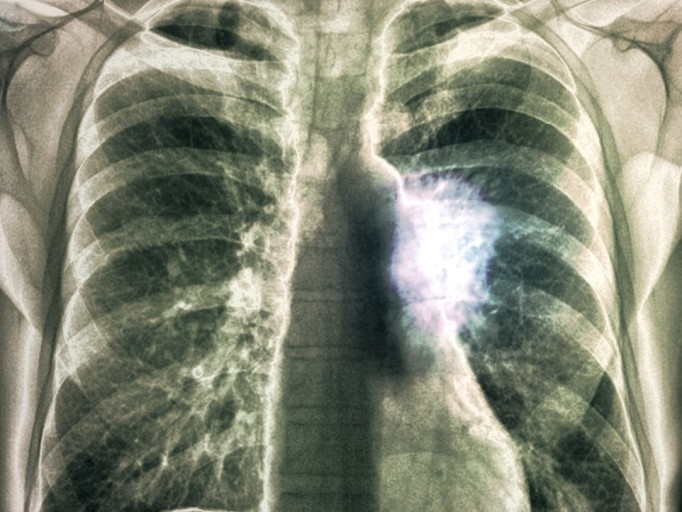

- 호흡 곤란 및 가슴 통증

- 설명: 폐렴의 가장 심각하고 중요한 증상입니다. 폐에 염증이 생겨 폐 기능이 떨어지면서 숨쉬기 힘들어지며, 얕고 빠른 호흡을 하게 됩니다. 심한 경우 가슴에 통증을 느끼거나, 옆구리가 결리는 듯한 느낌을 받을 수 있습니다.